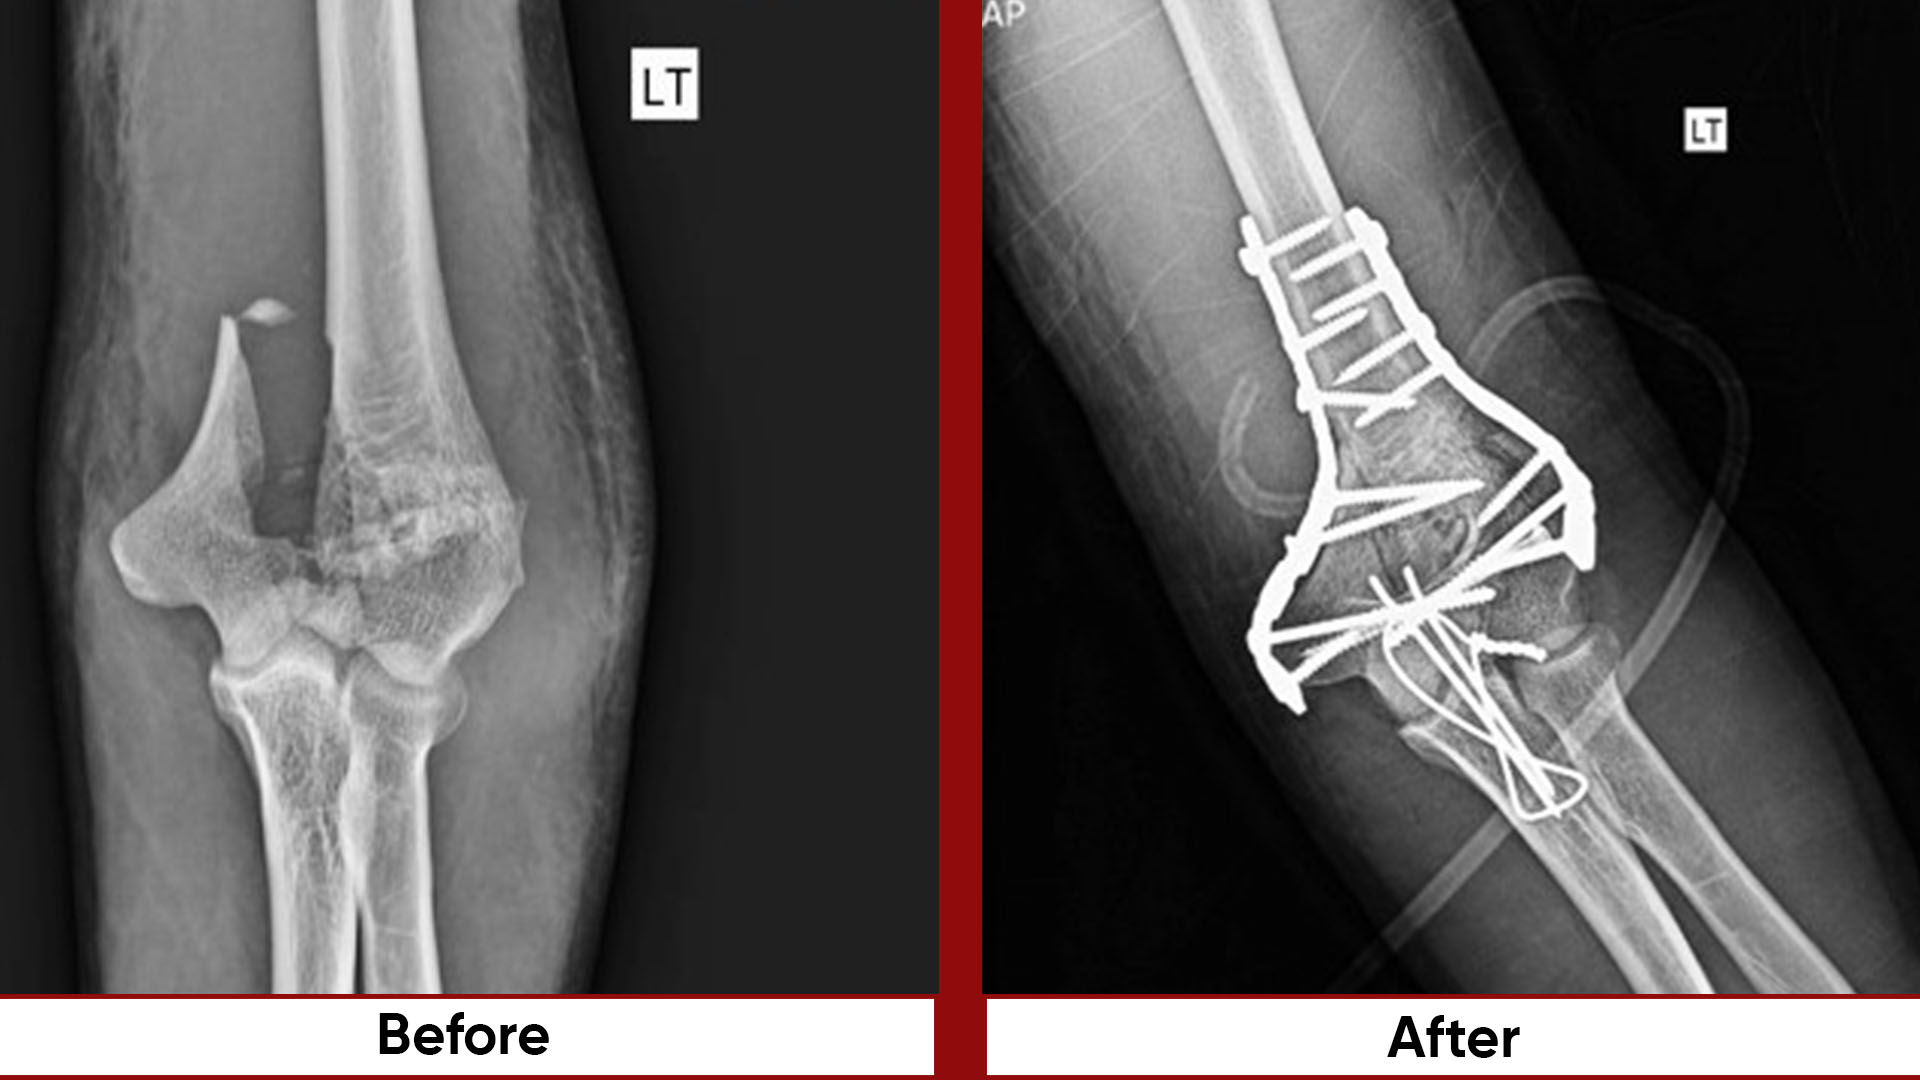

• Fracture Management (simple and complex trauma)

• Pelvic & Acetabular Fracture Fixation